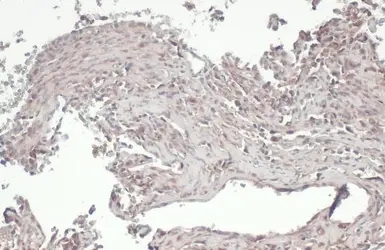

RIP3 antibody detects RIP3 protein at cytoplasm and nucleus by immunohistochemical analysis.

Sample: Paraffin-embedded human lung cancer.

RIP3 stained by RIP3 antibody (GTX131188) diluted at 1:500.

Antigen Retrieval: Citrate buffer, pH 6.0, 15 min